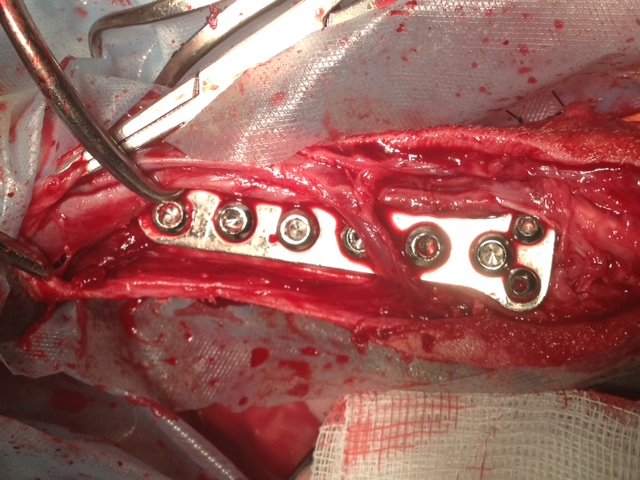

Wir danken herzlich für die Geldspenden, die dies alles erst ermöglicht haben - aber bitten auch dringend um weitere Überweisungen, denn wir mussten heute auch Griffin operieren lassen, der sich mit Kniescheibenproblemen herumplagte. Und weil Lucy auch Probleme zu haben scheint, haben wir sie heute mitgenommen zum Röntgen. Es stellte sich leider heraus, dass sie einen Kreuzbandriss hat, der ebenfalls operiert werden muss.